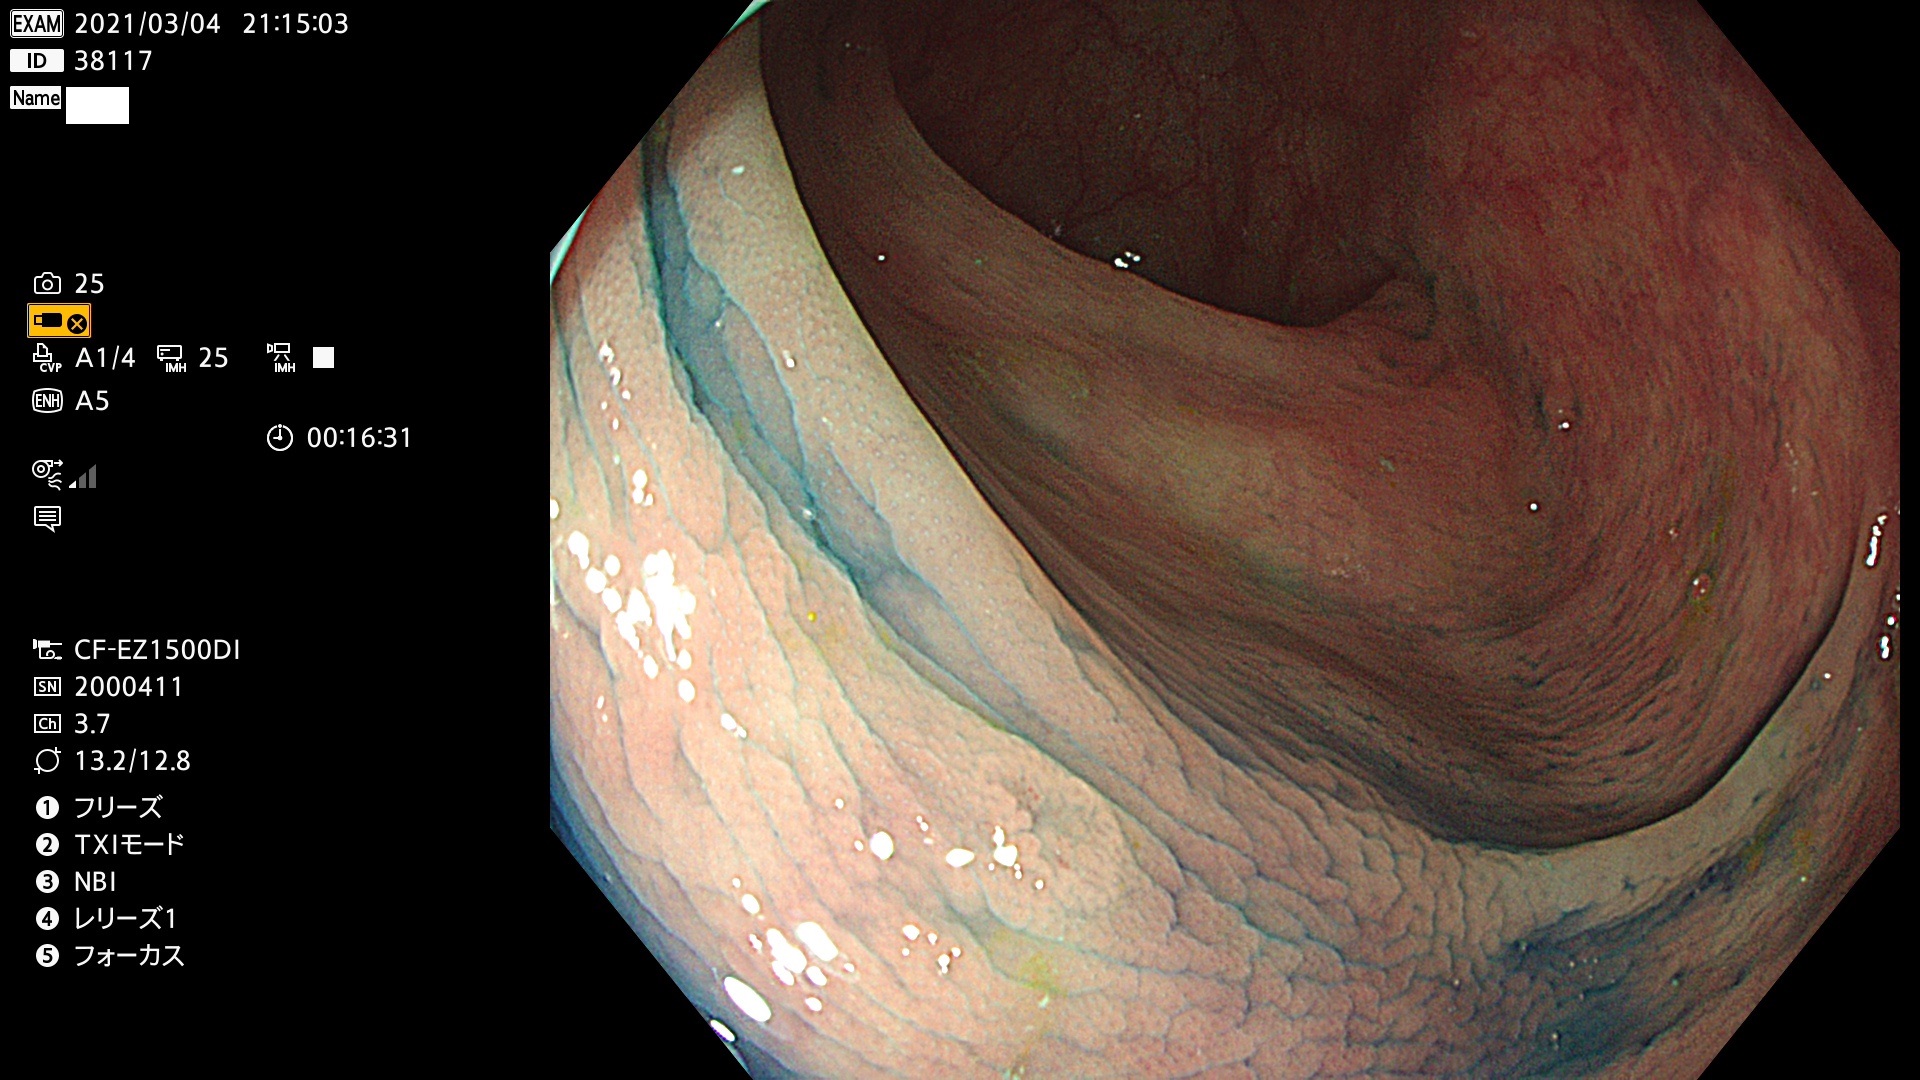

腺腫発見率 72 % (カルテ番号 38100〜38199の100名の方の検査結果で集計)大腸癌検診最新情報

以下のカルテ番号の方に腺腫(Adenoma,Group3〜5)が見つかりました(集計法)

38101 38103 38104 38106 38107 38108 38109 38110 38111 38112 38113 38114 38115 38117 38118 38122 38123 38124 38125 38126 38127 38128 38130 38131 38132 38135 38137 38138 38140 38141 38142(SSAPのみ) 38143 38144 38145 38146 38147 38148 38149 38150 38151 38152 38153 38154 38157 38158 38160 38161 38162 38164 38165 38166 38167 38168 38169 38172 38176 38177 38178 38181 38182 38183 38184 38187 38189 38190 38191 38192 38193 38194 38195 38196(SSAPのみ) 38198

発見困難で危険性の高い平坦型病変(上記100名より抽出) ![]()